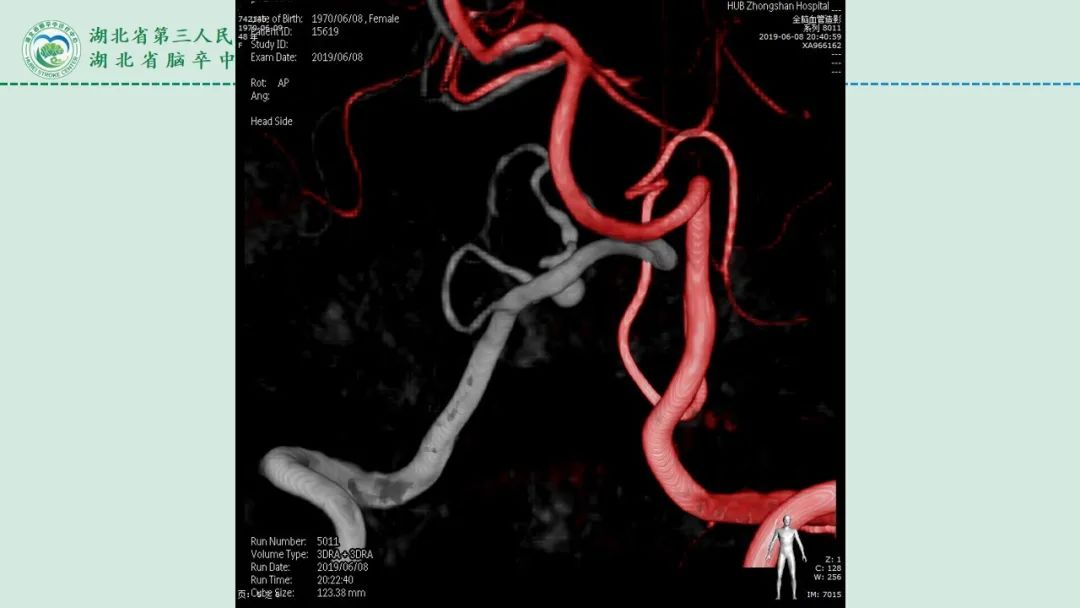

李俊教授团队:右侧PICA延髓扁桃体段多发动脉瘤

今日与大家分享的是《正海-妙术视界》第二百三十二期,由湖北省第三人民医院李俊教授团队带来的右侧PICA延髓扁桃体段多发动脉瘤,欢迎观看、分享。